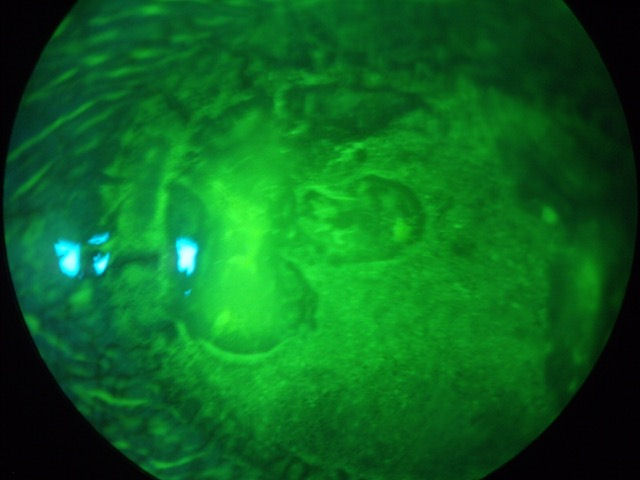

НОВИНКА! Добавлено 5/11/2015 . Ниже представлены 3 фотографии одного и того же глаза пациента, перенесшего две процедуры LASIK 10-12 лет назад. После второй операции LASIK у пациента произошло отслоение сетчатки и, как следствие, полная слепота на этом глазу. На снимке Visante OCT (первое изображение) вы можете видеть, что лоскут LASIK отделился от роговицы. На первом снимке (2-е изображение) вы можете видеть неоваскуляризацию роговицы - красные кровеносные сосуды, прорастающие в пораженную роговицу. Эпителий также отделяется от роговицы, как обои, отслаивающиеся от стены. Пузырчатая область в положении "7:00" - это буллезная кератопатия - жидкость под эпителием. Ближе к центру зрачка находится темная область углубления, или язва. На 2-й фотографии (3-е изображение), сделанной зеленым красителем, вы можете видеть, что отслойка эпителия простирается выше пузырька буллезной кератопатии, а чуть левее пузырька виден край лоскута LASIK. Щелкните по изображениям, чтобы увеличить их.